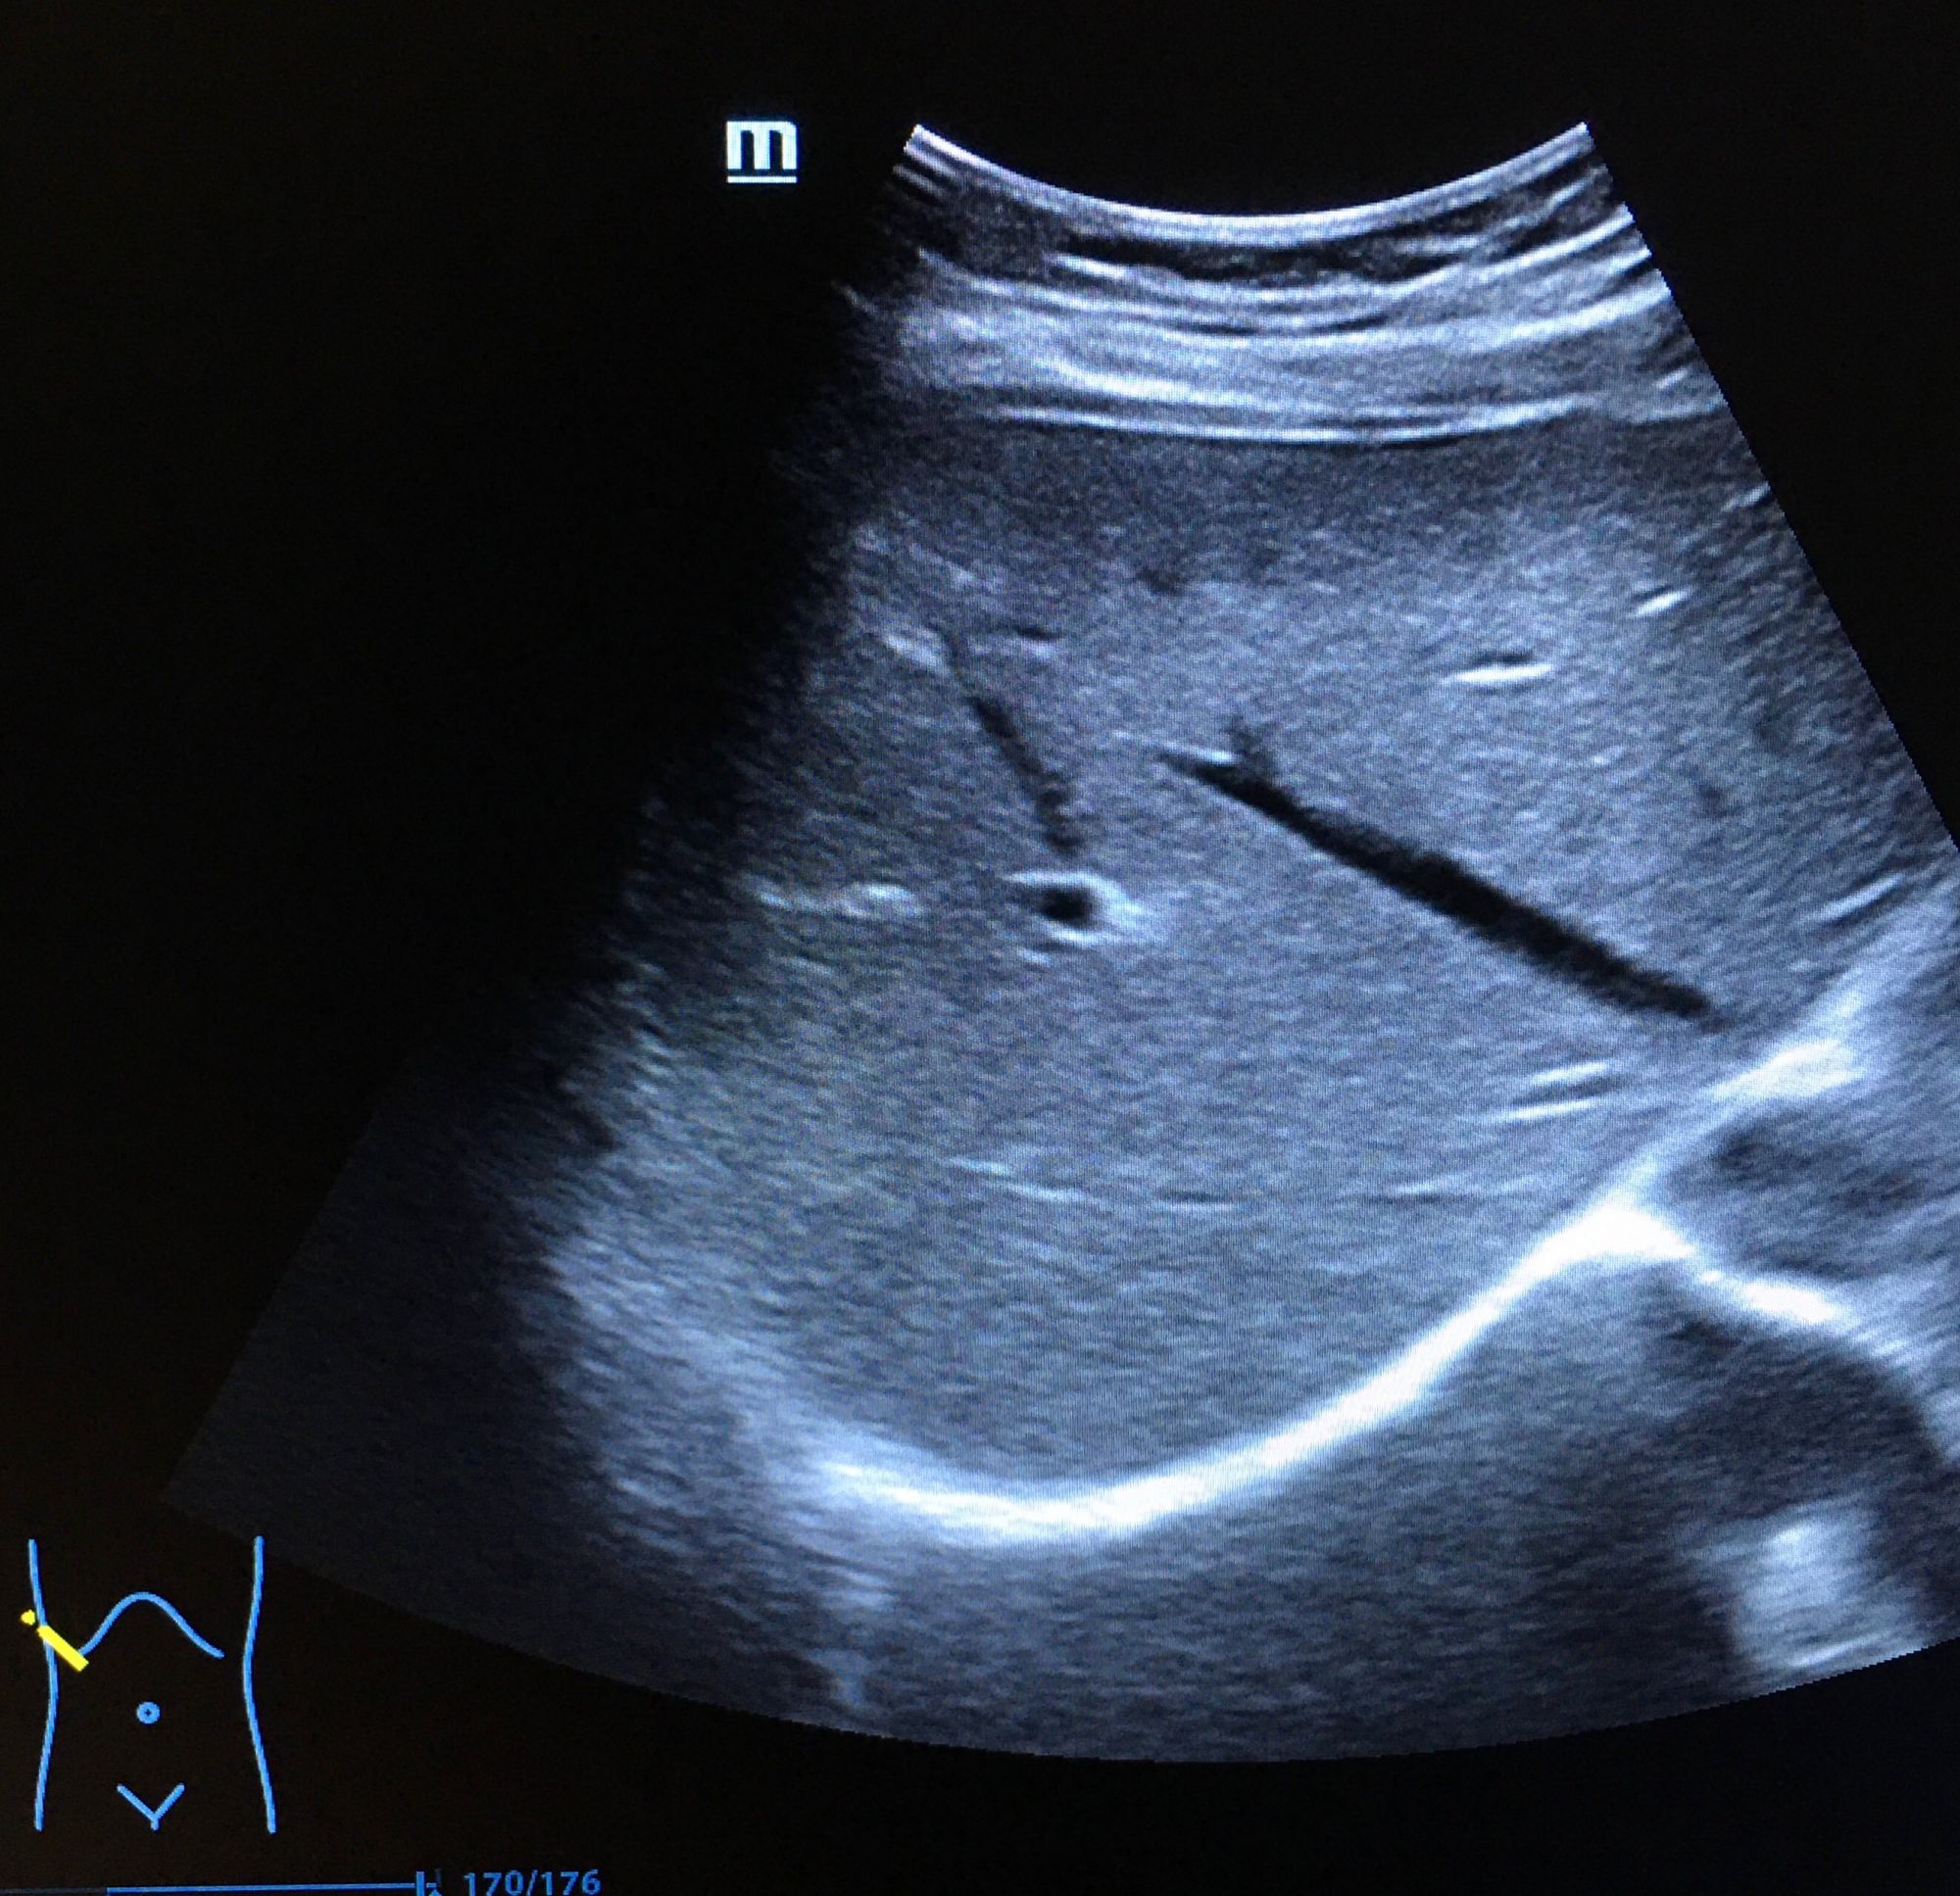

二、超聲成像

是一種基于超聲波的成像技術(shù)。超聲波在生物體內(nèi)傳播時,遇到不同的組織會產(chǎn)生不同的回聲信號,通過分析這些信號可以獲取生物體的內(nèi)部結(jié)構(gòu)和功能信息。超聲成像具有無創(chuàng)、無痛、無輻射等優(yōu)點(diǎn),因此在臨床診斷和生命科學(xué)研究中得到了廣泛應(yīng)用。

超聲成像